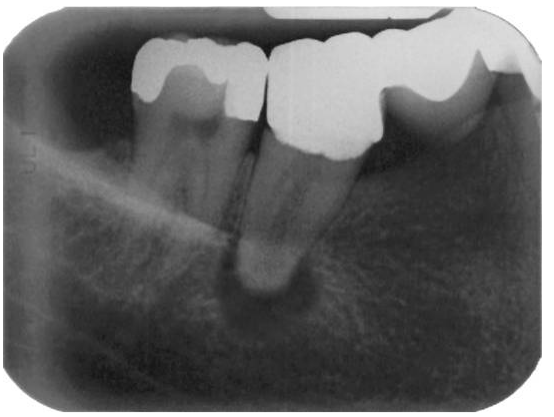

7.患者自述46牙齒喝水時會酸痛,平時偶有自發性疼痛,臨床檢查發現,46遠心側以探針探測 時會疼痛,無敲診痛,無觸診痛,牙齒周圍軟組織無腫脹,無明顯牙周囊袋,X光檢查如下 圖,則46根尖周圍的診斷,何者最適當?

(A)正常的牙根尖周圍組織 (B)急性發炎,無骨頭破壞吸收 (C)急性發炎,合併骨頭破壞吸收 (D)慢性發炎,尚無骨頭破壞吸收